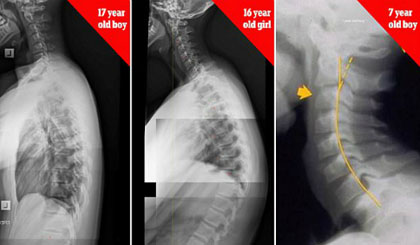

| Xương sống của bé trai 17 tuổi, bé gái 16 tuổi và bé trai 7 tuổi bị biến dạng do nghiện thiết bị điện tử. Ảnh: James Carter. |